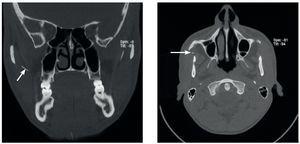

Un paciente de 35 años de edad acudió a la consulta de su odontólogo de cabecera por un cuadro de dolor agudo en el lado derecho de la mandíbula. La punta de la aguja se rompió durante la anestesia de conducción del nervio dentario inferior. No fue posible localizarla desde la cavidad oral. El paciente fue remitido para su diagnóstico y tratamiento urgente a la Clínica de Cirugía Maxilofacial de la Clínica Universitaria de Zúrich. Una ortopantomografía obtenida por el odontólogo de cabecera evidenciaba claramente la punta rota en proyección sobre la tuberosidad maxilar derecha (fig. 1). A su llegada a la clínica el paciente estaba asintomático. En la exploración clínica no se logró localizar con precisión la aguja. Se practicó una tomografía computarizada para una evaluación exacta. En la TC se observó la aguja rota en la zona del tejido adiposo y la cara inferior del músculo masetero directamente en medial del arco cigomático y en la parte anterior de la rama ascendente de la mandíbula (fig. 2).

Figura 1. En la ortopantomografía realizada por el odontólogo de cabecera se observa una imagen radioopaca de densidad metálica de 20 mm de largo que se proyecta sobre la tuberosidad maxilar derecha.